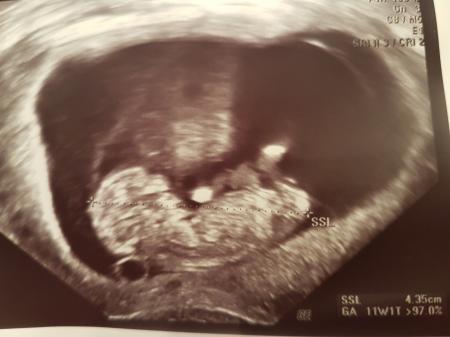

Hey Mädels, nun habe ich endlich meinen lang ersehnten Termin hinter mir. Habe mir schon so viele Gedanken gemacht, wollte mich aber nicht verrückt machen und zwischendurch gehen. Nun dachte ich heute "schön bei 10+4 zum US" und siehe da: Krümel ist schon so groß, dass sie vordadiert hat und ich nun einen Sprung in die 12. Woche gemacht hab Hab ein Bild von meinem Gummibärchen angehängt. Bin überglücklich und kann mich nun endlich drauf einlassen und die bisherige vorsichtige Skepsis weicht nun Vorfreude

Bild zu Zurück von der FÄ und Überraschung :-) - Forum für August - Mamis

Ach wie toll!!! Das sind ja echt super Neuigkeiten. Freut mich für dich und ein echt schönes Bild hast du da bekommen :)